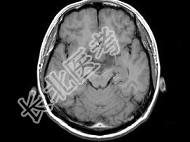

- 单项选择题男,27岁, 头痛、双眼视力下降、多饮、多尿4个月,根据所提供图像, 最可能的诊断是 ( )

A、颅咽管瘤

B、垂体瘤

C、生殖细胞瘤

D、胶质瘤

E、神经鞘瘤